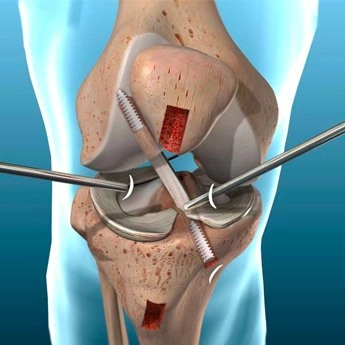

Antes de mais nada, a cirurgia de menisco representa uma das soluções mais indicadas para pacientes que sofrem com lesões no joelho e não obtêm melhora com tratamentos conservadores. Dessa forma, o procedimento devolve mobilidade, reduz a dor e permite que a articulação volte a funcionar de maneira eficiente. Quando […]

Antes de mais nada, a artroscopia no joelho representa uma técnica moderna e minimamente invasiva que auxilia no diagnóstico e tratamento de diferentes lesões articulares. Dessa forma, pacientes que sofrem com dores persistentes, inflamações ou limitações de movimento encontram nesse procedimento uma alternativa segura e eficaz. Indicações da artroscopia no […]